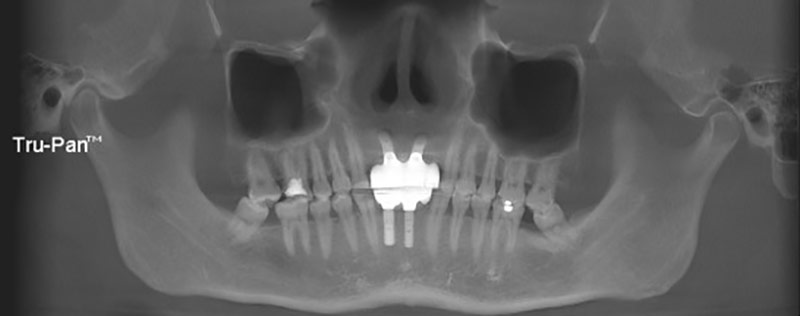

辅助检查:CBCT示:12、11、21、22、42、41、31、32牙槽骨吸收达根尖三分之一

图4术前CBCT全景视图